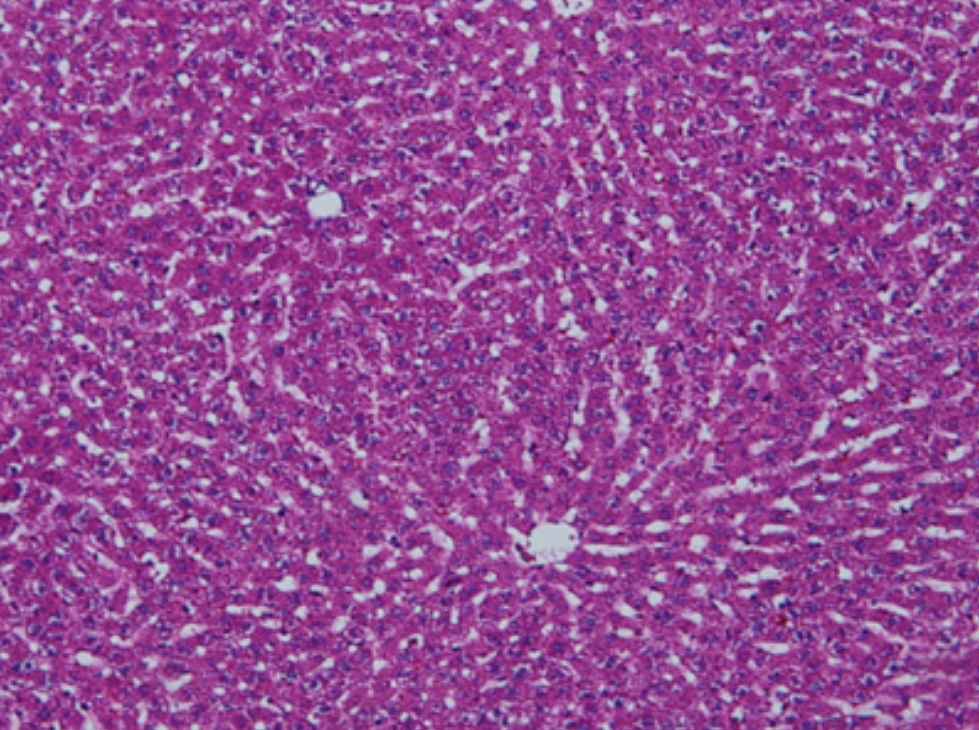

HE染色,全称苏木精-伊红染色法(Hematoxylin and Eosin staining),是最常见的组织切片染色技术之一,用于在显微镜下观察和分析组织或细胞的结构和形态。虽然HE染色是最常见且最基础的染色技术之一,😭但在实验过···

HE染色,全称苏木精-伊红染色法(Hematoxylin and Eosin staining),是最常见的组织切片染色技术之一,用于在显微镜下观察和分析组织或细胞的结构和形态。

虽然HE染色是最常见且最基础的染色技术之一,😭但在实验过程中,很容易出现各种情况导致染色切片质量参差不齐。所以,小编根据以往实验经验,给大家整理归纳出了15个HE染色中的常见问题,还包含问题原因分析以及解决方法哦~

形成原因:切片经梯度乙醇处理后没有完全脱水,导致二甲苯透明、中性树胶封固后残留大量水分。 解决方法:首先移去盖玻片,用二甲苯溶解封固剂如中性树胶,再将切片置入无水乙醇内,待切片重新脱水完全后,用二甲苯透明处理,中性树胶封固。要注意所有用于脱水和透明的液体,在使用一定时间后,应及时更换。 二、细胞核呈红、棕色 形成原因:苏木精染色液过度氧化,切片在苏木精染液染色后返蓝不足。 解决方法:每次染色之前检查苏木精染色液的染色能力,发现苏木精染色液氧化过度应及时更换。此外,切片经苏木精染色后,要给切片以足够的蓝化时间,蓝化过程可用流水、温水、弱碱性溶液(如稀氨水或0.2%碳酸氢钠)等处理。 三、切片在脱蜡后出现大片白色斑点 形成原因:由于烤(烘)片温度太低,切片上的组织蜡膜在脱蜡前没有充分烤(烘)融化。或是因为切片在二甲苯液中停留时间不足,或二甲苯使用过久,造成的脱蜡不彻底。 解决方法:若是由于切片烤(烘)温度低所致,可以先用二甲苯去除切片上的封固胶,然后重新用二甲苯脱去切片上的石蜡,再进行后续染色。若是由于切片在脱蜡的二甲苯中停留时间不足或脱蜡二甲苯使用过久浓度不足所致,则需将切片退回到二甲苯中,停留较长时间,或更换二甲苯液体重新脱蜡,再入乙醇重新脱二甲苯,入0.5%盐酸水溶液褪色后,重新HE染色。 四、细胞核苍白暗淡,即苏木精染色太淡 形成原因:切片在苏木精染色液停留时间太短;苏木精染色液过度氧化,失去染色能力,不能再继续使用;分化步骤处理时间过长;固定不及时。此外值得注意的是,若骨组织细胞核暗淡,大多是脱钙过度造成的。 解决方法:切片重新染色。如果组织在酸性固定液(如Zenker、Bouin)或非中性缓冲甲醛液固定时间过长,细胞核染色能力将减弱,需增加其在苏木精染色液的时间,或用一些方法增加组织的嗜碱性,以改善细胞核的着色。例如,上述组织玻片可以使用Weigert铁苏木精染色液。如果组织是用Zenker液固定的,可将切片脱蜡后放在5%碳酸氢钠溶液3~4h,流水冲洗5min后染色。如果组织是用Bouin液固定的,可将切片脱蜡后放在5%碳酸锂1h,流水冲洗10min后染色。 五、细胞核过染,苏木精染液占据了细胞质 形成原因:玻片在苏木精染色液停留时间过长,或是切片太厚、分化步骤时间太短。 解决方法:如果不是因为切片太厚(用显微镜仔细上下微调,只有一二层细胞核层次),就需将切片进行脱色、漂白、重新染色,适当调整染色和分化时间。但如果确定是由于切片太厚导致的细胞核过染,则需要重新切片。 六、伊红着色淡 形成原因:可能是伊红染液pH值大于5,也可能是蓝化液残留过多,切片太薄,或是切片经伊红染色后在乙醇脱水时间过长。 解决方法:检查伊红染液pH值,必要的话,用乙酸将其调节在4.6~5.0之间,从而使伊红染色色彩艳丽。此外,确保每次蓝化步骤完成后,使用的弱碱性溶液被充分洗去,玻片上没有残留的弱碱性溶液。最后,检查切片的厚度,且脱水时不要让切片在低浓度乙醇中停留时间过长,因为含水多的低浓度乙醇会将切片伊红的颜色分化掉。 七、细胞质过染、分色不足 形成原因:伊红染色液浓度太高,特别是存在焰红燃料、四溴四氯荧光素钠。切片在伊红染色时间过长,或是切片在伊红染色后经乙醇脱水步骤时时间太短,而使乙醇分化伊红的作用不能产生,都能够使细胞质过染。 解决方法:适当稀释伊红染色液,减少伊红染色时间,或使切片在乙醇脱水等步骤时,停留时间相对均匀。同样,也要检查切片的厚度是否合适。 八、切片中出现蓝黑色沉淀物 形成原因:苏木精染色液中的金属膜黏附在玻片上。 解决方法:染色前仔细过滤苏木精染色液,建议使用半氧化苏木精染色液,如Gill苏木精染色液,可以避免过多的金属膜产生。 九、光镜下切片某些区域难以聚焦 形成原因:盖玻片上可能有封固切片的封固剂。 解决方法:移去盖玻片,重新用干净的盖玻片封片。检查切片封片方法,是人工手工封法,还是机器自动封法,如有问题及时调整。 十、封固剂从盖玻片与载玻片之间的缝隙回缩 形成原因:盖玻片弯曲或不平整,或是封固剂含二甲苯过多,稀释过度。 解决方法:移去盖玻片,重新找一张盖玻片,用干净的封固剂封片。如用手工封片法,保证在封固结束时,封固剂容器盖子为紧闭状态。且尽量使用小的容器盛装封固剂,一旦封固剂太黏稠,就可以选择废弃。 十一、细胞核呈灰蓝状态 形成原因:可能由于组织处理温度过高、过热,在液体石蜡中停留的时间过长。或是固定时间太短后,直接在高浓度的乙醇中进行了脱水处理。 解决方法:理论上来说,仅在组织浸蜡步骤才进行加热,组织不能在热蜡液中停留太久。如果由于某些原因不能进行下一步包埋处理,可将组织连同塑料包埋盒一并放置在室温空气中,冷却凝固,以备包埋。待需要包埋时再重新加温直至石蜡融化即可。组织在处理前必须确保固定良好,脱水最好能从低浓度的乙醇开始。 十二、类色素的点状结晶和黑色光滑细胞核 形成原因:这种裸核改变是因为切片封片前放置在空气中的时间太长,以至于二甲苯挥发,切片干燥。 解决方法:移去组织切片上的盖玻片和封固剂,重新处理。将切片水洗数分钟,然后重新脱水、透明、封固。封片过程中要保持组织切片的轻度湿润,尽量不要让其干燥。 十三、染色过淡或过浓 解决方法:如果染色过淡,可以增加染色剂的浓度、延长染色时间或更换新鲜的染色剂;如果染色过浓,则应减少染色剂的浓度或缩短染色时间。 十四、切片出现叠加褶皱 形成原因:新购买的玻片洁净度不够、用镊子撑开切片时操作不够熟练未能平整伸展,或玻片表面有油脂,切片粘贴不牢。另外,烤片时间不足、烤片温度过低或切片过厚造成切片脱落,都会造成重叠或有皱褶的情况。 解决方法:新购买的玻片最好能用硫酸清洁液浸泡一晚,然后流水冲洗干净。在适宜的温度下烤片时间宁长勿短,保证有充足的烤片时间和温度。另外,切片刀要锋利,才能切出厚薄适宜的切片,保证切片不会因为过厚而脱落。 十五、组织残缺不全或有刮划痕迹 形成原因:组织残缺不全是由于切片时修整蜡块时深度不够、组织没有全部暴露于切面。切片的刮划痕迹是由于切片刀的刀锋有缺口、包埋的组织有异物,或是钙化组织、骨组织及包埋石蜡有沙粒造成的。 解决方法:修整蜡块时保证组织块全部暴露于切面,切片时保证切片刀的锋利没刀口。同时在组织取材时去除手术异物和钙化组织。最后,骨组织要完全脱钙,这样可以保证切片的完整和平整美观。 *注:由于实验中导致结果出现误差的原因多种多样,以上内容仅供参考,具体根据实际情况进行判断。